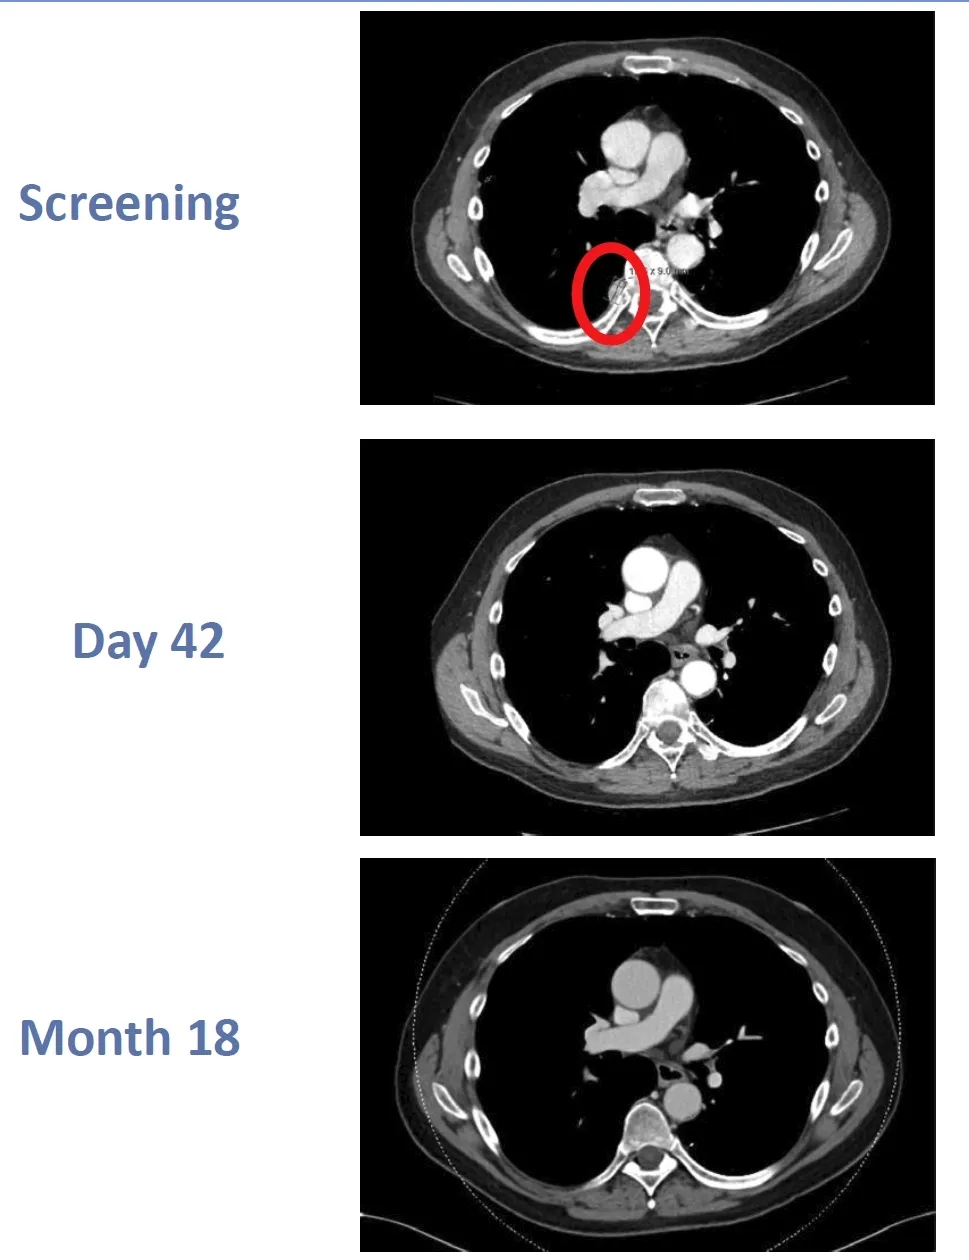

该患者经CTX130治疗后,获得部分缓解(PR),更为惊喜的是,他在治疗第3个月竟然实现完全缓解(CR),而且在第18个月复查时,依然保存CR状态!据悉,这是异基因CAR-T细胞,首次实现这种持久的完全缓解(CR)!

图1 该患者在回输CTX130前、治疗第42天、第18个月时的影像学对比